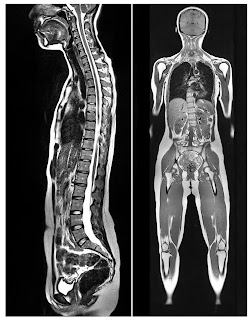

In simplistic terms, having a full-body access comports to the fact that everything is connected in one way or another. Tumor cells start somewhere, but they can spread almost anywhere they want. If we find a cancer in stage one (which usually means confined to the organ of origin) what happens afterwards is to ask if it is IN FACT confined to that organ, or if it has spread somewhere else. This is called staging.

After a cancer is detected, patients often go into a panic asking "What stage is it? ... Is it metastatic?" Working with the conventional MRI or CT of the past, they would have to wait to get a brain MRI, then a chest, abdomen, pelvis study and a bone scan etc. With our technology, we already have all that. We've routinely found people with stage one cancer as part of early detection. This is a good basis where you want to find it. From here, searching 'full body' is the best next step to make sure that it's not anywhere else in the body. Using an MRI with diffusion, we can see it all. (See full feature #1)

An MRI is known as the most detailed imaging available for scanning a tumor anywhere in the body. Creating a treatment strategy becomes more effective when you know no areas have been overlooked. Patients and physicians both have a higher and more confident level of understanding about what they're dealing with. A great example is confirming that the pounding headache that a patient suffers from after a diagnosis of cancer is stress related, not due the fear of a metastasis...Whole body MRI coverage can preempt this concern.